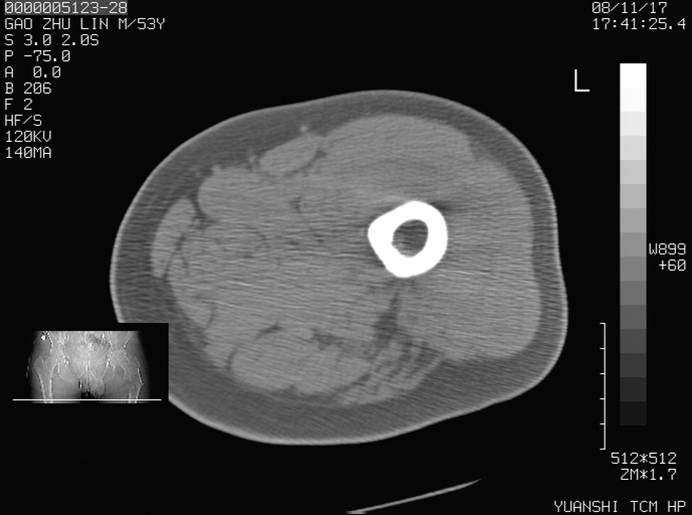

标题: CT16696:M53Y,左股骨上段骨折。 [打印本页]

标题: CT16696:M53Y,左股骨上段骨折。

左股骨上段外伤1个小时,左股骨上段疼痛。村医以腰椎间盘病变给以按摩及理疗数天。

左股骨上段粉碎性骨折

左股骨上段粉碎性骨折,不排除病理性骨折可能。

考虑骨肉瘤伴病理骨折

考虑:骨肉瘤伴病理骨折.

病理性骨折,考虑转移所致.